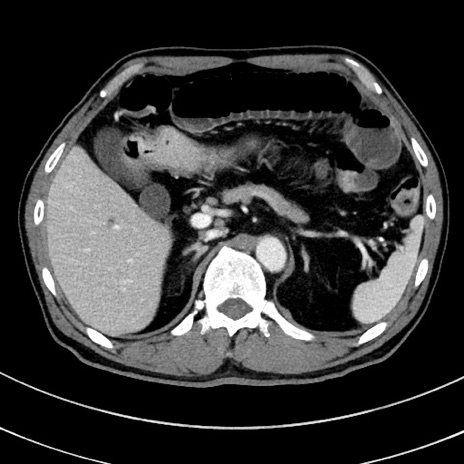

症例8(横断像)

【症例】 60歳代男性

【主訴】 黒色吐物

【現病歴】 4日前から嘔気自覚、2日前の朝食後にも嘔気あり、自分で手で嘔吐反射起こし嘔吐したところ血が混ざっていたため受診。

【既往歴】 5年前汎発性腹膜炎を伴う急性虫垂炎で手術、高血圧、前立腺肥大症、高脂血症

【身体所見】 腹部正中に手術癩痕あり 腹部平坦・軟圧痛なし膨満感あり

【データ】WBC 8400、CRP 4.54